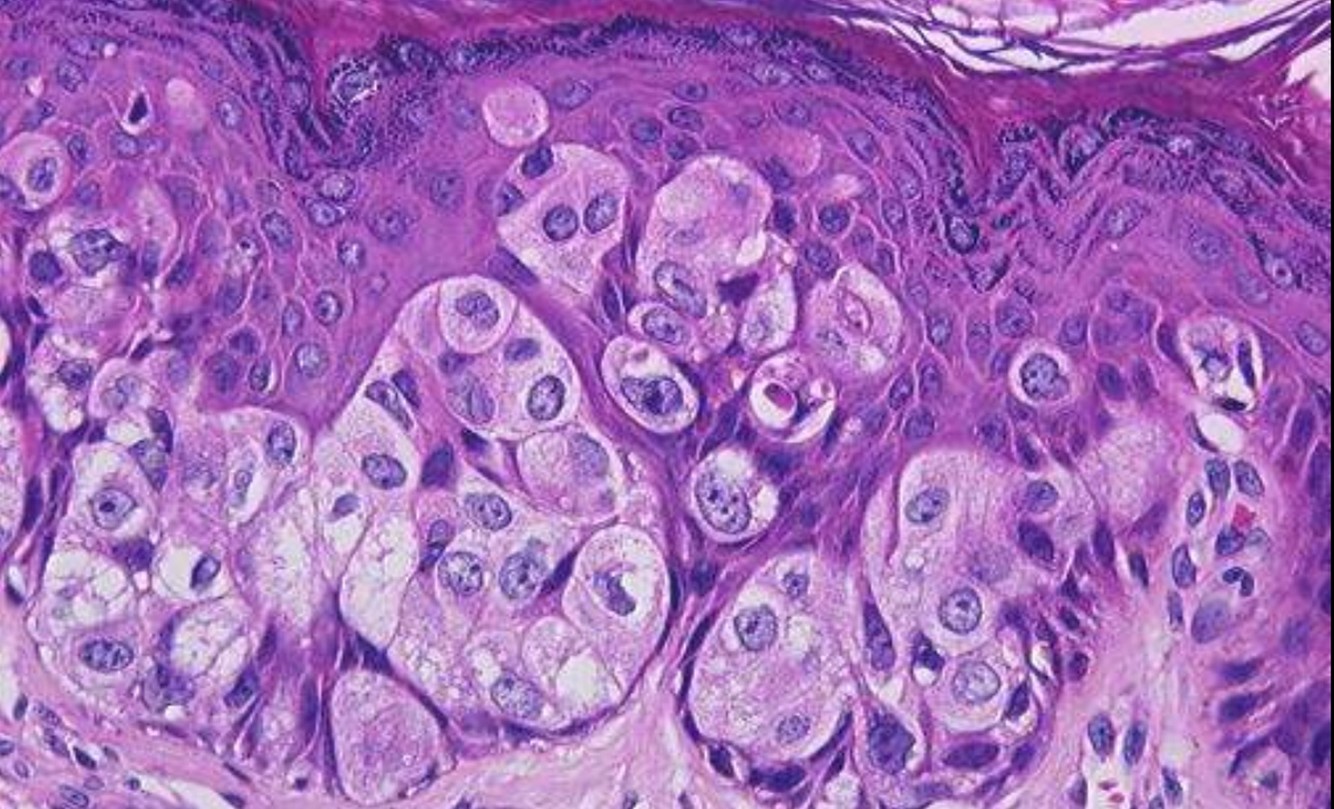

VULVAR INTRAEPITHELIAL NEOPLASIA

• HPV associated type

• Younger age

• Multifocal

• CIN

• Smoking